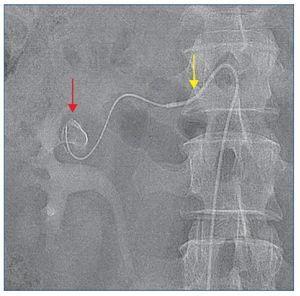

Paciente varón de 61 años, fumador con antecedentes patológicos de HRV; controlado por nefrología y en tratamiento con tres antihipertensivos cada 24 h (enalapril 20 mg, hidroclorotiazida 12,5 mg y atenolol 50 mg). Hepatopatía crónica por enolismo y múltiples episodios de cólico nefrítico, por los que se solicita ecografía abdominal y del sistema urinario, en la que se objetiva aneurisma densamente calcificado de 9,8 mm de rama anterior del riñón derecho que posteriormente es confirmado mediante tomografía computarizada —TC— (figura 1).

Figura 1. Aneurisma calcificado de la rama anterior del riñón derecho.